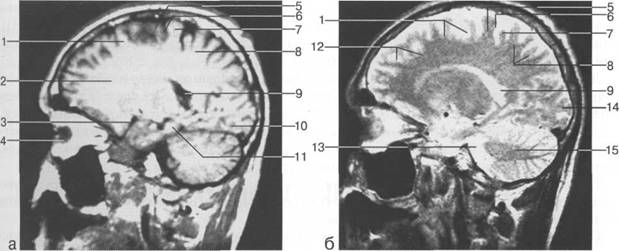

Задняя череп 13513u2010n 85;ая ямка представляет собой часть основания череп 13513u2010n 72;, ограниченную централь

Следует отметить, что в настоящее время оптимальным методом исследования структур задней череп 13513u2010n 85;ой ямки является МРТ, которая, в отличие от КТ, лишена артефактов от кост

Мозжечок заполняет практически весь объем задней череп 13513u2010n 85;ой ямки. Его поперечный раз

IV IV IV IV III IV

височная доля; 17 - полушарие мозжечка; 18 - |

Следует остановиться на анатомии подпаутинных пространств задней череп 13513u2010n 85;ой ямки IV 20 мм. Между основанием череп 13513u2010n 72; и нижней поверхностью мозга от большого затылочного отверстия вдоль ската и спинки турецкого седла простирается задняя базальная цистерна. В зави IV